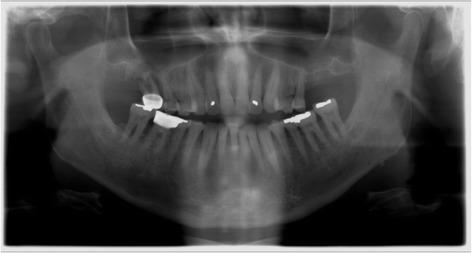

Patients with resorbed edentulous alveolar ridges in the posterior maxilla often require lateral window sinus augmentation procedures prior to implant placement. Lateral window sinus augmentation procedures can produce incomplete bone augmentation as consequence of surgical and healing complications producing unusual and complex sinus anatomy. Although incomplete bone formation after sinus augmentation has been described in a previous case reports, this is the first case report that describes grafting these compromised sites prior to implant placement.

A 65-year-old male patient with no known medical conditions presented with severe chronic localized periodontitis and a combined periodontal-endodontic lesion affecting three first molars. Initial ridge preservation and lateral window sinus augmentation resulted in incomplete bone formation and complex sinus floor anatomy on both right and left sides. A dilating balloon technique on one side and a palatal approach on the other side were utilized for additional sinus augmentation using particulate allograft and resorbable collagen membranes. Healing was uneventful, and implants could be placed and restored at all sites. Periodontal maintenance was conducted every 3 months, and the implants have been in function and periodontally healthy for 2 years.